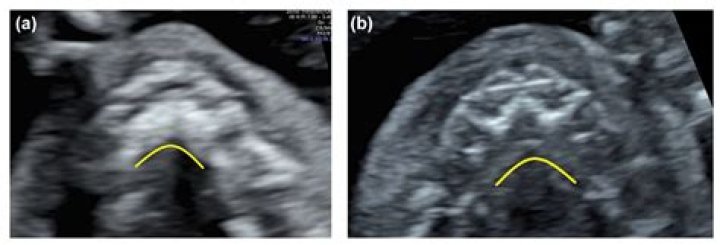

A regular ultrasound scan cannot reliably identify a cleft palate, either by itself or along with a cleft lip. If you have received a diagnosis of 'cleft lip and palate' from a regular ultrasound scan, it's very likely that what was actually found was a cleft lip and gum.

A cleft lip is usually picked up during the mid-pregnancy anomaly scan done when you're between 18 and 21 weeks pregnant. Not all cleft lips will be obvious on this scan and it's very difficult to detect a cleft palate on an ultrasound scan.

In most cases, a prenatal ultrasound can detect cleft lip alone or cleft lip and palate as early as 16 weeks into a pregnancy. The diagnosis is then confirmed at birth with a detailed visual assessment and physical examination.

3D ultrasound in high-risk women resulted in a detection rate of 100% for cleft lip, 86% to 90% for cleft lip with palate and 0% to 89% for cleft palate only.